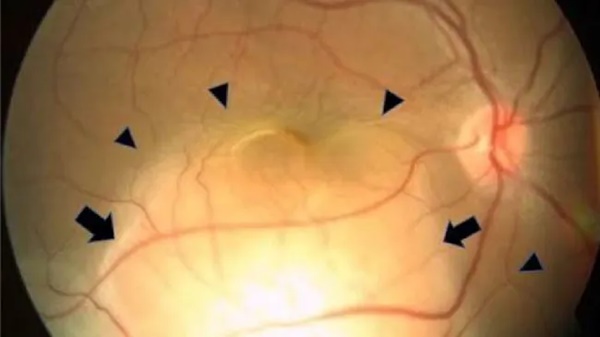

Tuy nhiên, khi kiểm tra kỹ hơn, các bác sĩ phát hiện có một khối lớn màu trắng vàng phát triển ở phía sau mắt phải của cô. Chất lỏng cũng tích tụ dưới võng mạc, phần nhạy cảm với ánh sáng của mắt, khiến nó bị bong ra. Có một vết thương tương tự, nhỏ hơn ở mắt trái của cô, nhưng võng mạc của nó vẫn còn nguyên vẹn.

Hình ảnh mắt phải của bệnh nhân, cho thấy tổn thương ung thư và bong võng mạc